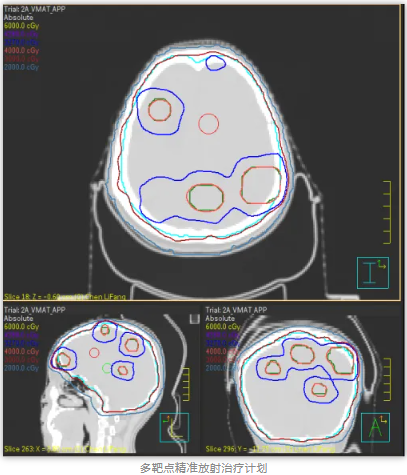

王女士最近很苦“脑”,发现肺部肿瘤复发转移到了脑部,新发病灶多达6颗。为提高放疗疗效、减少放射损伤,肿瘤科团队提出采用新近开展的 “多靶点精准放射治疗技术(MTPRT)”进行治疗。相较于全脑放疗而言,该技术不容易脱靶,能够更有效保护靶区外的正常脑组织,降低患者的副反应。

在肿瘤中心专家团队指导下,放疗医生、物理师、治疗师、护士等各专业人员紧密配合,王女士经历了“患者定位—大孔径CT下模拟定位—多靶点肿瘤计划设计—治疗前的计划验证和位置验证—适时治疗”的放疗流程,目前已经顺利完成了一个疗程的放射治疗,其间无明显不适,脑部的转移瘤也基本消失。

MTPRT是一种先进的放疗方法,旨在使用CT、MRI和PET等影像技术精确识别和定位多个肿瘤靶点。针对不同肿瘤靶点的生物学特性,制定优化的放射剂量分布,同时照射多个肿瘤靶点。在治疗过程中,通过实时影像监控患者和肿瘤位置变化,动态调整治疗方案。该技术综合利用影像引导放疗(IGRT)、立体定向放射治疗(SBRT)和调强放射治疗(IMRT)等手段,通过高精度影像技术和先进的计算算法,实现对复杂肿瘤的有效治疗,同时最大限度地保护周围健康组织。该技术代表了放射治疗领域的前沿发展,具有广泛的临床应用前景和重要的研究价值。